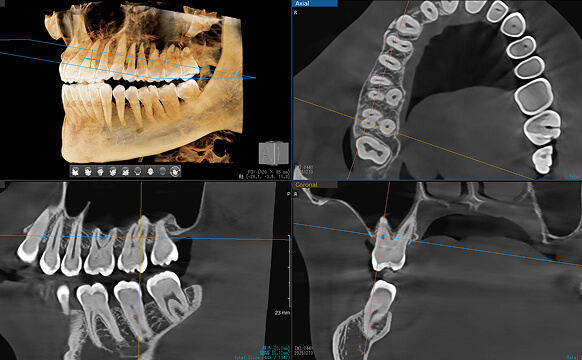

CTによる3次元診断

骨の厚みや神経の位置を立体的に把握し、治療計画を正確に立てます。

必要に応じて骨造成や歯ぐきの再生もご提案します。

CT撮影による精密な診断と立体的な計画

まずCTで親知らずと移植先の部位を撮影し、歯根の形・長さ、移植部の骨の厚みや角度などを三次元的に正確に把握します。

これにより、移植が可能かどうかを高精度に判断できます。